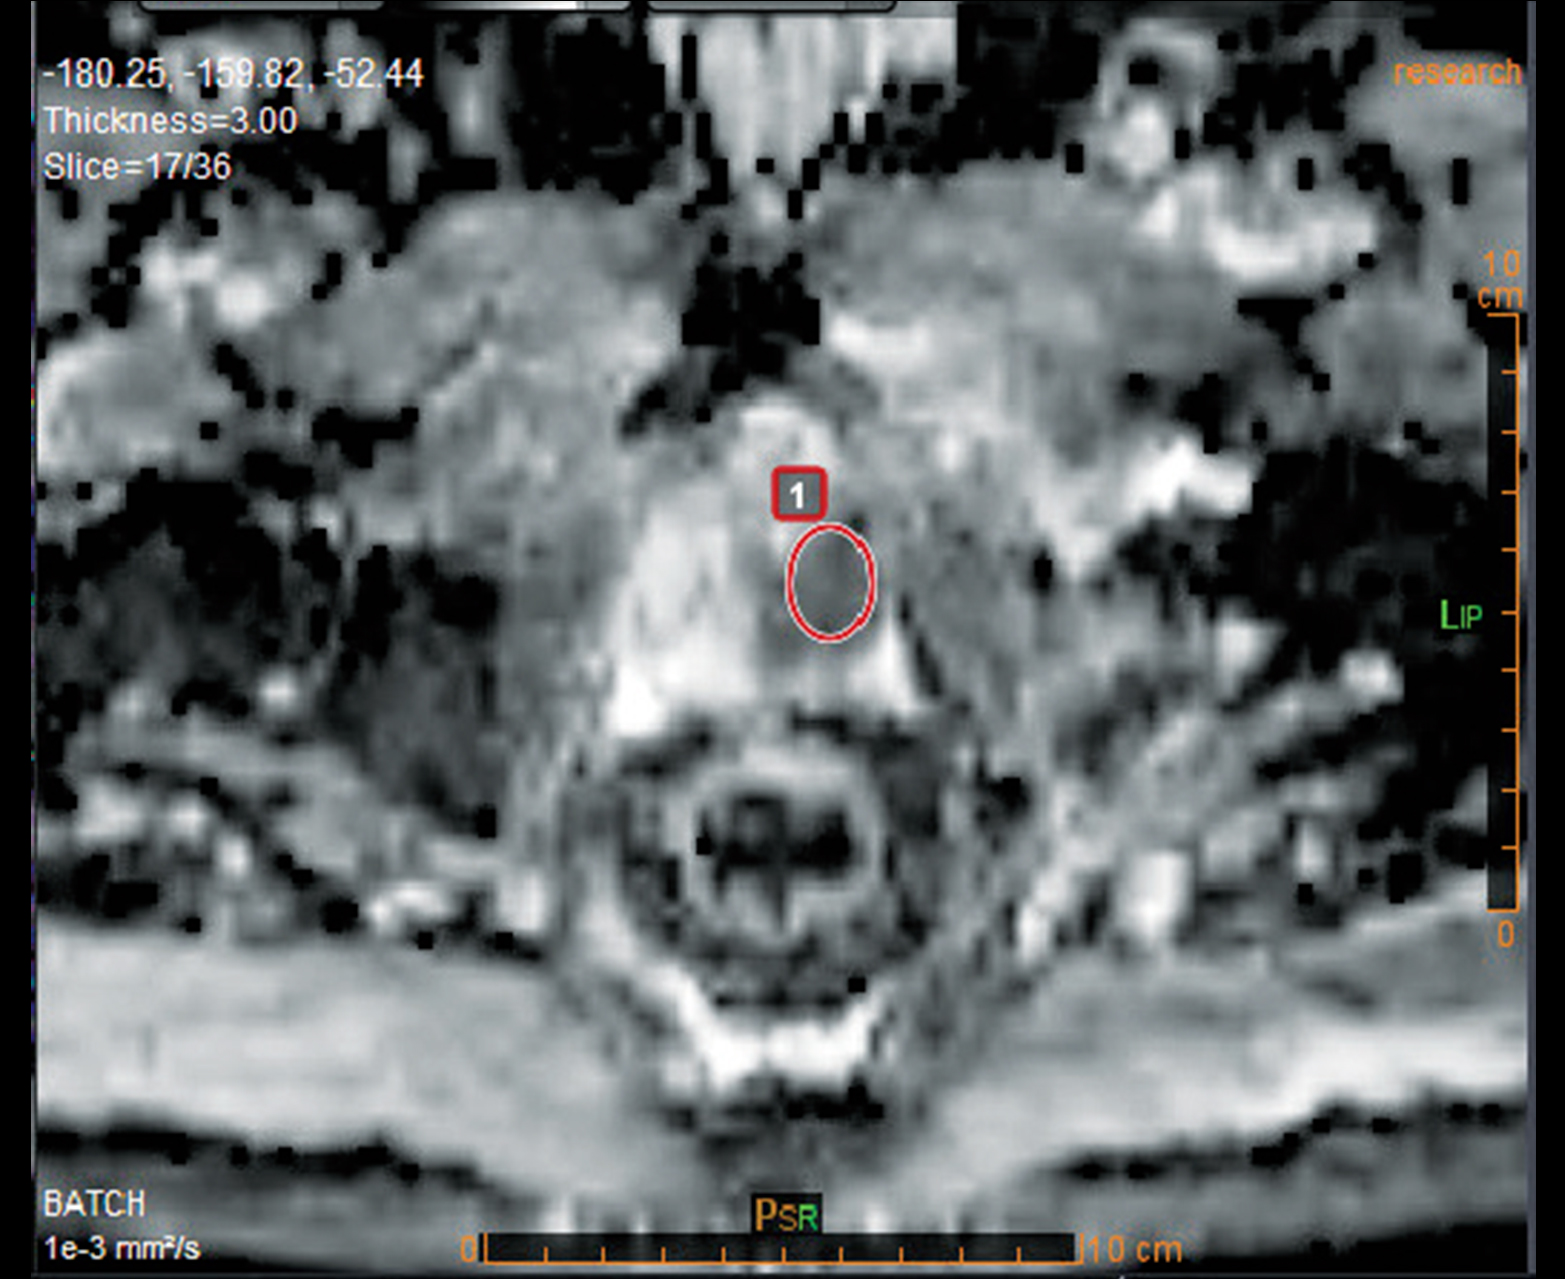

Расчет АЦП и других качественных и количественных карт